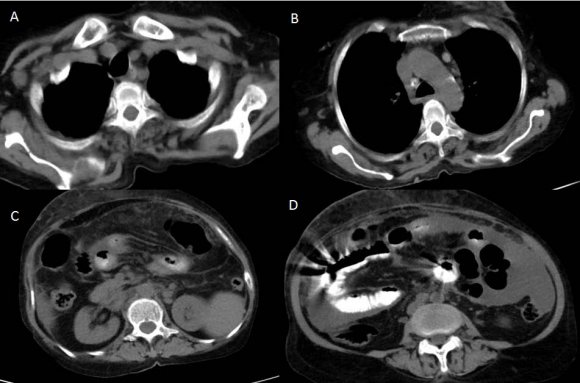

CT scan of the abdomen and pelvis (Figures: 4-8) showed changes of fatty infiltration in the liver. Multiple well-defined lymph nodes of size 1 to 2 cms were noted at portahepatis, peripancreatic region, celiac axis, left renal hilum, preaortic and para-aortic regions, precaval and paracaval regions and in right internal iliac region. Most of the lymph nodes showed peripheral enhancement with central hypodense areas of necrosis. A conglomerated matted lymph nodal mass of size 35 x 24 mm noted in the precaval region. Multiple ill-defined and nodular soft tissues infiltrate noted within the mesentery. Moderate ascites noted with mild peritoneal enhancement without septations. Ileo-caecal junction and other bowel loops appeared normal. IVC distal to renal veins showed persistent filling defect of size 10 (Anteroposterior) x 16 (Transverse) mm extending over a length of 67mm with peripheral enhancement in contrast study extending to right common iliac vein suggestive of IVC and right common iliac vein thrombosis.

Figure 4. Figure 4 :Abdominal

4Figure 4: Contrast-enhanced CT scan of the abdomen showing lymph nodes at the celiac axis (A, B), in precaval region (C), in the left para-aortic and preaortic region (D) showing peripheral enhancement with central hypodense areas of necrosis.

Figure 5. Figure 5 :

5Figure 5: Contrast-enhanced CT scan of the abdomen showing lymph nodes at left para-aortic and inter-aortocaval region (A, B), a filling defect in IVC suggestive of IVC thrombosis (C, D).

Figure 6. Figure 6 :

6Figure 6: Contrast-enhanced CT scan of the abdomen showing lymph nodes in precaval region (A) with thrombosis in IVC (A-C) extending right common iliac vein (D)